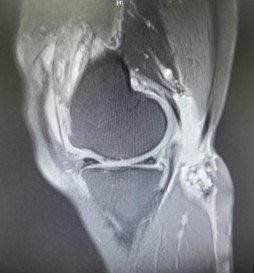

On magnetic resonance imaging of the right knee, degenerative changes and joint effusion were also noted as with a lesion in synovial membrane. The findings in the popliteal fossa were also suggestive of a popliteal cyst (Figure 1).

MRI of right knee joint showed degenerative changes, effusion and synovial membrane lesions in the knee joint along with presentation at popliteal fossa suggestive of a popliteal cyst.